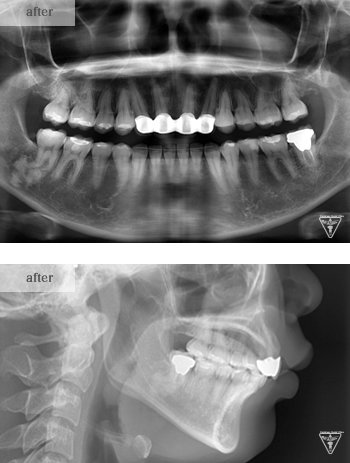

治療後